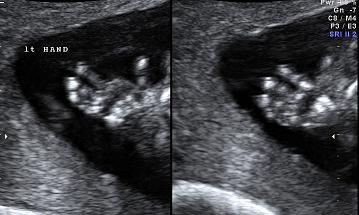

香港结构超声波照片

结构性超声波, 四维 香港, 四维结构性超声波 结构性超声波, 四维 结构性超声波, 四维 香港, 四维结构性超声波 结构性超声波, 四维 香港, 四维结构性超声波 结构性超声波, 四维 结构性超声波, 四维 结构性超声波, 四维 香港, 四维结构性超声波 结构性超声波, 四维 香港, 四维结构性超声波 结构性超声波, 四维 结构性超声波, 四维